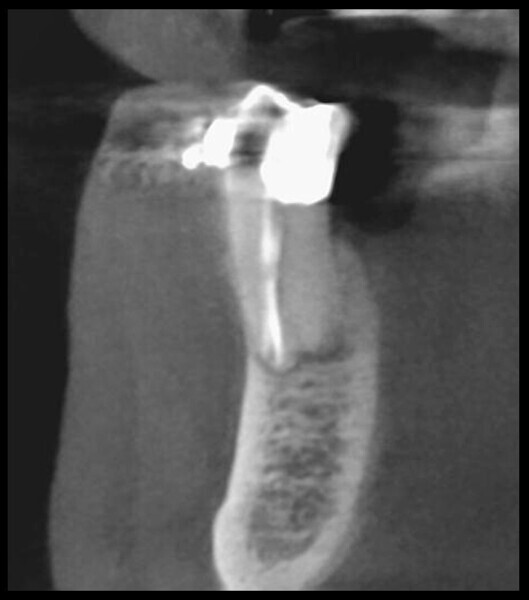

Use of 3D technology in the diagnosis and treatment of endodontic disease